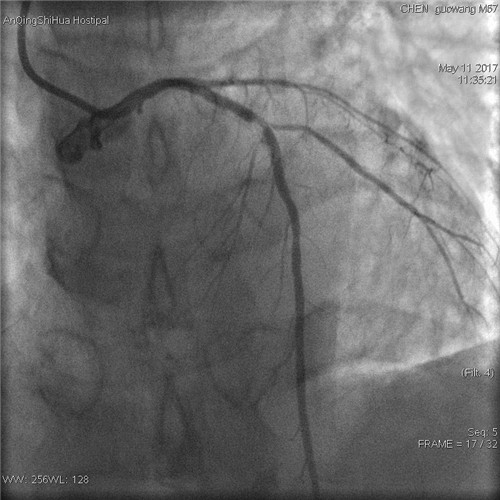

術(shù)前 回旋支完全閉塞

術(shù)前 前降支支架內(nèi)80%局限性再狹窄